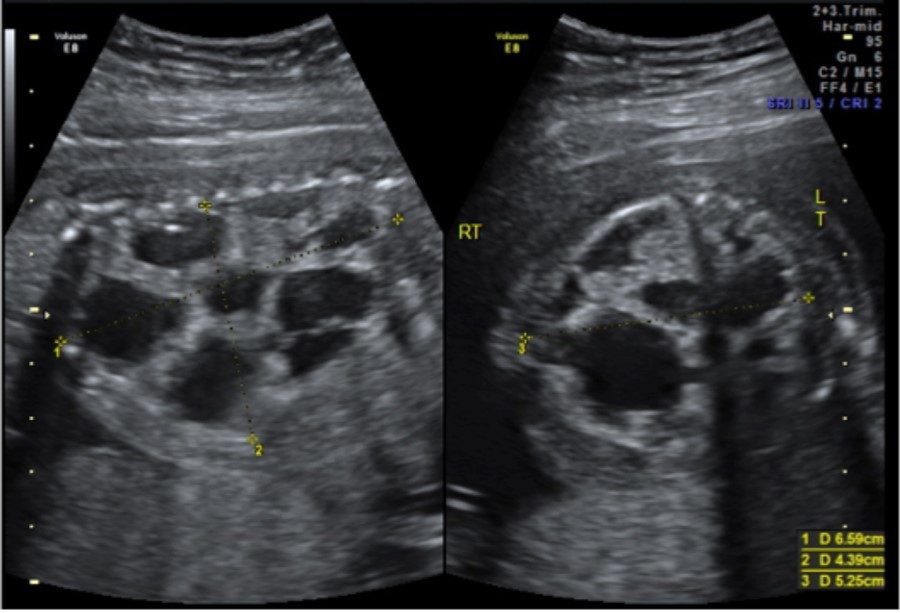

A 33-year-old gravida 1 initially presented for a detailed ultrasound in our office with fulminant fetal hydrops and a noted mass in the left chest. Initial evaluation included maternal viral studies (negative parvovirus, CMV, toxoplasmosis), maternal karyotype (46XX), and amniocentesis (46XX, microduplication in the 16p11.2 region). Given concern for CPAM and hydrops at 20 weeks and 3 days, the patient was referred to a fetal therapy center. Ultrasound at the fetal therapy center showed an estimated fetal weight of 824 grams (>97th percentile) and fetal hydrops (scalp edema of 8mm, skin edema of 4mm, and ascites of 14mm). The diaphragm was intact and the maximal vertical pocket was 6.8 cm. The left chest mass measured 6.6 x 5.3 x 4.4 cm and was multiloculated with microcystic and macrocystic lesions (type 1); the dominant cyst measured 4.0 x 3.2 cm, Figure 1. Secondary to mass effect, the heart was severely displaced into the right chest with a CVR of 3.9cm2. There was no noticeable peristalsis of the cystic structures and no systemic identifiable arterial blood supply. Fetal echocardiogram showed a structurally normal heart significantly shifted in the right chest. After extensive counseling, the patient opted for administration of antenatal corticosteroids and thoraco-amniotic shunt placement. The patient received betamethasone 12mg intramuscularly prior to shunt placement at 21 weeks and 4 days and 21weeks 5 days. Two double pigtail Harrison thoraco-amniotic shunts were placed by inserting a 13 Ga cannular-trocar into the maternal abdomen and uterus (the first shunt into the largest cyst (left, anterior, inferior) and the second into an additional dominant cyst (anterior, central portion of the mass). Both cysts drained completely after insertion. Epidural anesthesia with IV sedation were used as well as tocolytics as needed during the procedure. The post-procedure CVR was 1.3cm2 with decreased mass effect on the heart. Post-operative plan consisted of genetic consultation, fetal MRI, and serial monitoring of the CVR.

Figure 1.CPAM noted at initial fetal surgery consultation; sagittal view on the left and transverse view on the right

CPAM noted at initial fetal surgery consultation; sagittal view on the left and                 transverse view on the right